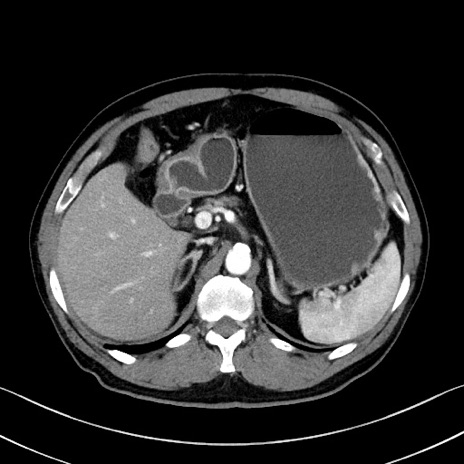

症例35(横断像)

【症例】70歳代 男性

【主訴】腹部膨満、嘔吐

【現病歴】昨日より腹部膨満感出現。本日増悪し、仙痛出現。嘔吐あり、受診。

【既往歴】糖尿病、胆摘後

【身体所見】BP 149/80mmHg、HR 74/min、BT 35.9℃、腹部:膨満、軟、圧痛なし。腸雑音減弱あり。上腹部正中切開瘢痕あり。

【データ】WBC 13500、CRP 1.72